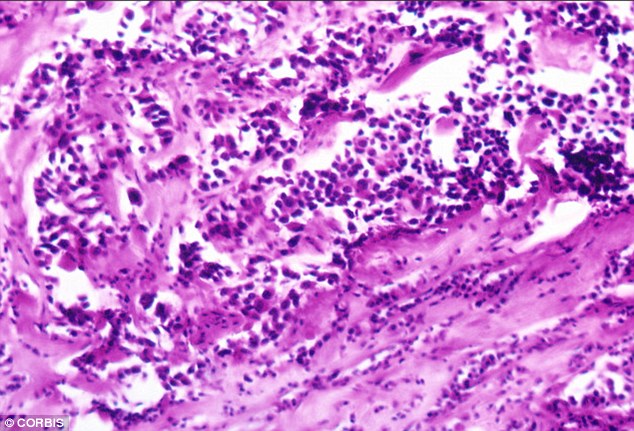

This is because mammograms can pick up a type of low-grade breast cancer called duct carcinoma in situ (DCIS). This is contained just in the milk ducts and has not spread into any of the surrounding breast tissue – about 60 per cent of DCIS cases are picked up by routine breast screening.

Around half of these cancers turn out to be harmless. It is my view that too many healthy women are harmed by breast cancer screening.

Worst of all were the unexpected high numbers diagnosed with duct carcinoma in situ (DCIS), a condition we rarely saw before screening began.

Many of these cases were multifocal and ended up with a mastectomy, yet they may well have turned out to be harmless.

We were soon to learn that 20 per cent of the cancers diagnosed in Butterfly Walk were DCIS, yet before we opened our doors they amounted to less than one per cent of our practice.